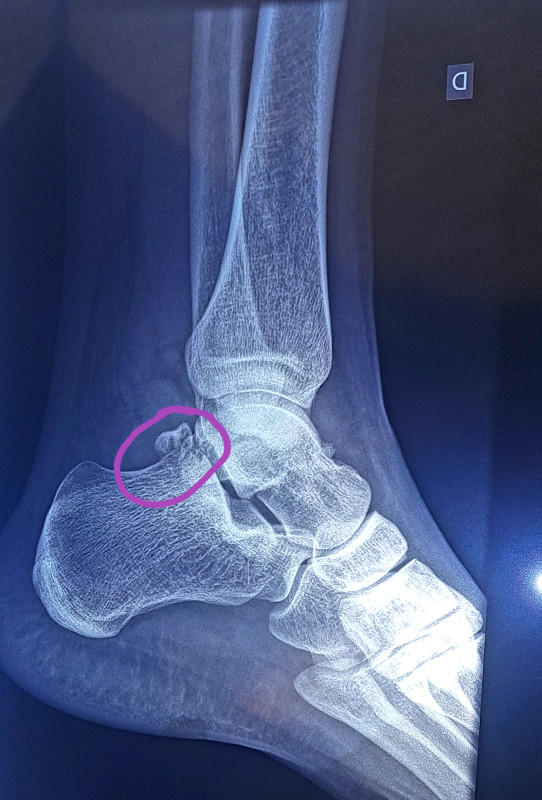

Mai 2019, grosses, grosses douleurs à la cheville qui est monstrueuse, on ne distinguait même plus ma maléole. Suspicion d'infection, PDS, écho, radio, IRM et enfiiiin on découvre cela :

Petit os trigone, ce qui n'est pas spécialement rare (6 à 7% de la population) mais qui ne pose que très rarement problème. J'ai aussi énormément de kystes (à l'IRM, ils ont mis 45mn à voir et avec deux injections de produit) dûs probablement aux frottements.

On appelle cela le conflit/syndrome du carrefour postérieur. Typique des pratiquant•es de foot, de danse ou de natation avec palmes.